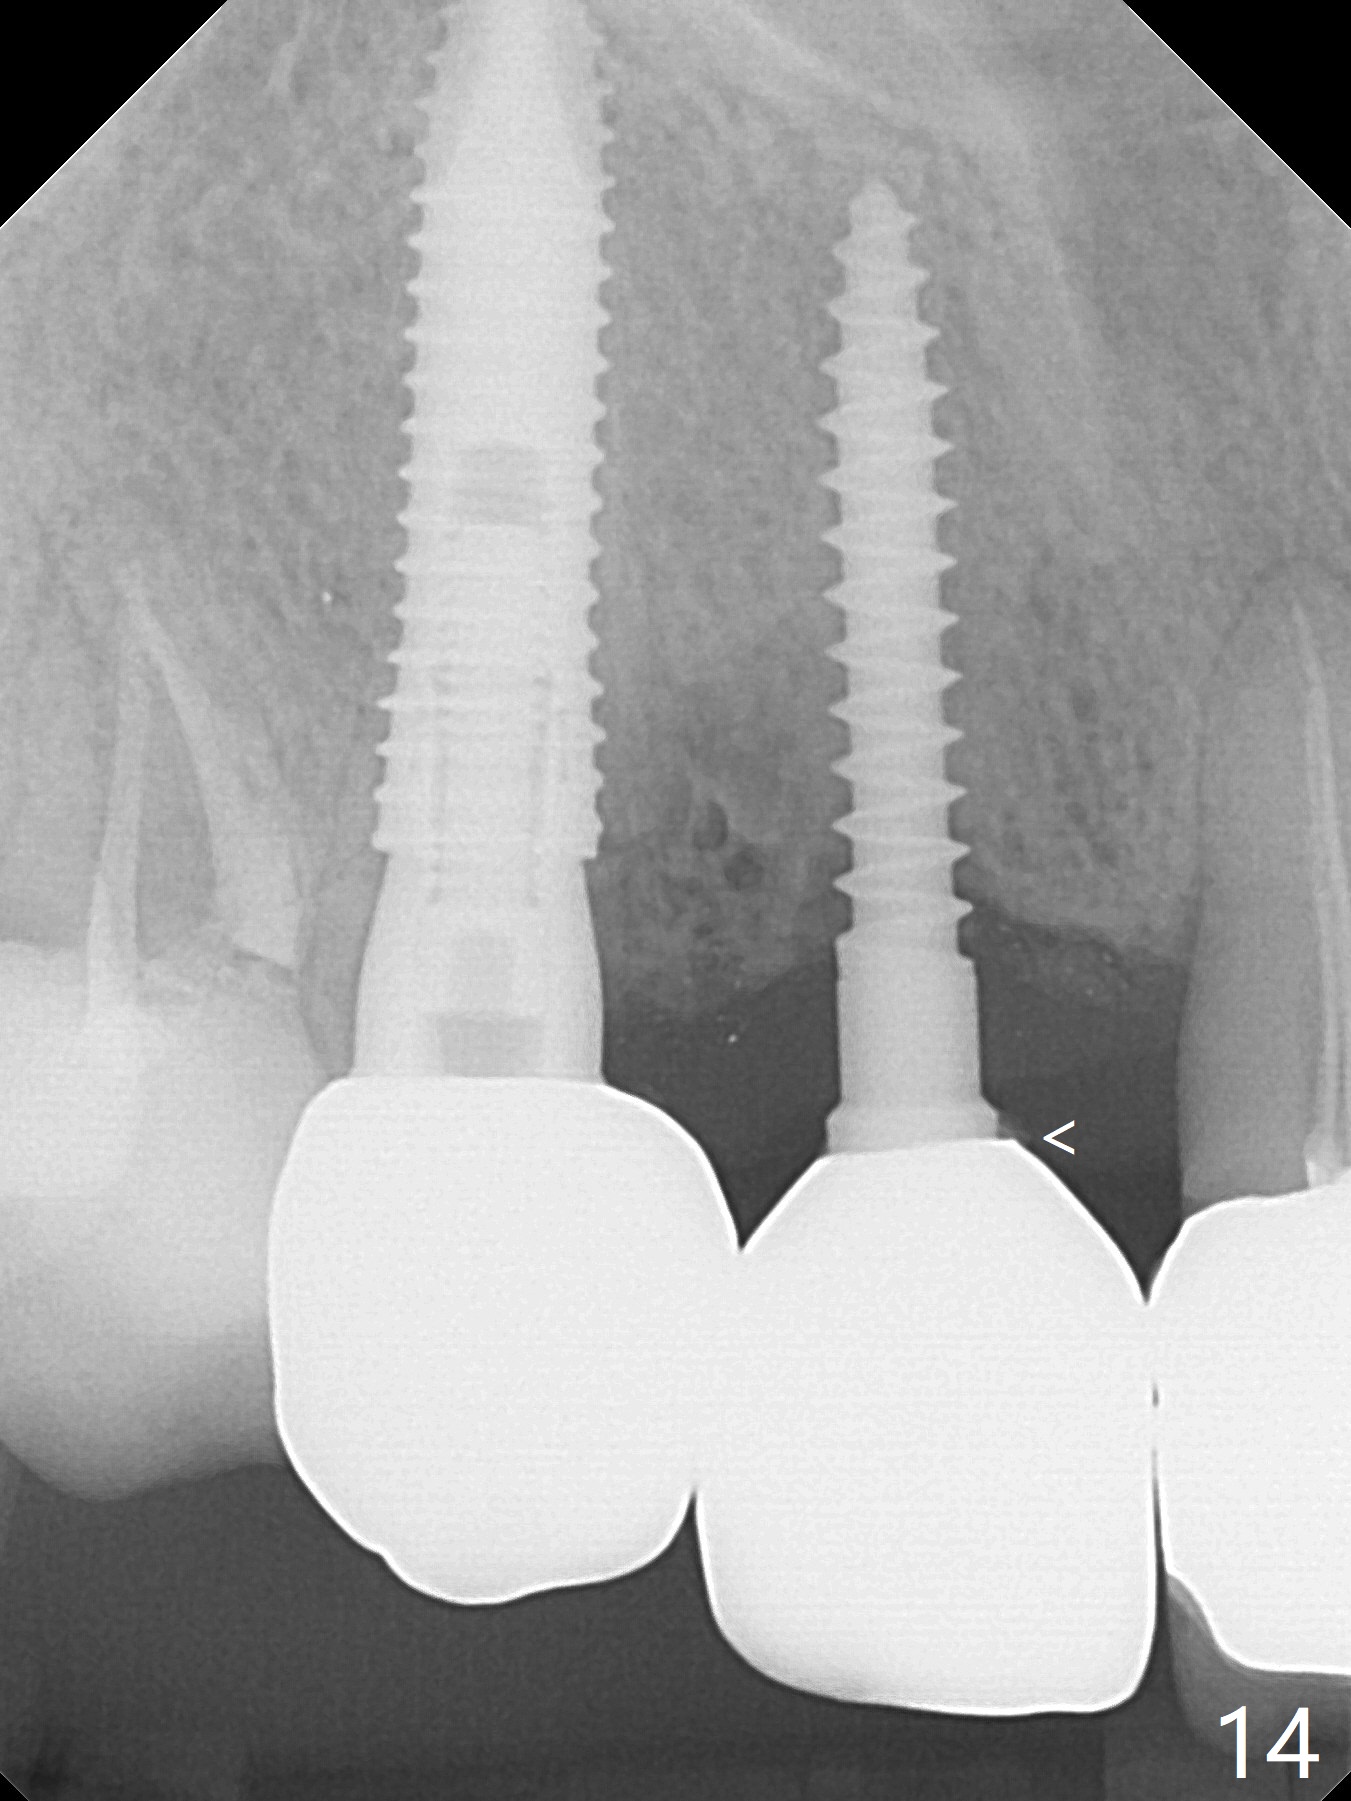

When the bridge is sectioned between #7 and 8, the tooth #6 is found non-salvageable (Fig.1). Incision shows the atrophic buccal plate at #7 (Fig.2 arrowheads); to prevent the same feature from happening at #6 with thin buccal plate, the most buccal portion of the root is preserved (socket shield (Fig.2-4: *)). The initial osteotomy is established in the palatal slope at #6 (Fig.5 circle) with 1.5 mm drill (Fig.6,7). A portion of the root is visible in Fig.6 (arrowheads). After sequential osteotomy with 2 mm, 3 mm (Fig.8) and 3.2 mm drills, a 4x15 mm implant is placed (Fig.10). To accommodate the cross bite, the coronal portion of the implant (Fig.9 white circle) is positioned close to the socket shield. It appears that the shield prevents the implant from encroaching the buccal plate.

Since the ridge at #7 is ~ 4 mm, a 2.5x14 mm 1-piece implant is placed (Fig.8) after 1.2 mm (Fig.7), and 1.5 mm drills at 12 mm and 2 mm drill at 8 mm. Later the implant is placed deeper (Fig.10). There is no bone loss 7 or 12 months postop, respectively (Fig.11,12). After Diode gingivectomy, there is papillary formation (Fig.13). No provisional is provided after impression (with the abutment torqued at #6) for oral hygiene. With access holes at #6 and 7, crowns are bonded with minimal residual cement (Fig.14 <, which is removed later). There is no hard (Fig.15,16) or soft (Fig.17 *) atrophy 26 months postop, i.e., 13 months post cementation, due to the presence of socket shield (Fig.15 <, as compared to Fig.1). In fact the tooth #8 has mobility and fremitus (short root/poor crown/root ratio, Fig.16); occlusal adjustment is done 13 months post cementation. The crown is dislodged 2 years 1 month post cementation; a prefabricated post is being tried in (Fig.18). There is no atrophy, bone loss or infection at #6 (with socket sheath (*)) or 7 two years 5 months post cementation (Fig.20-27).